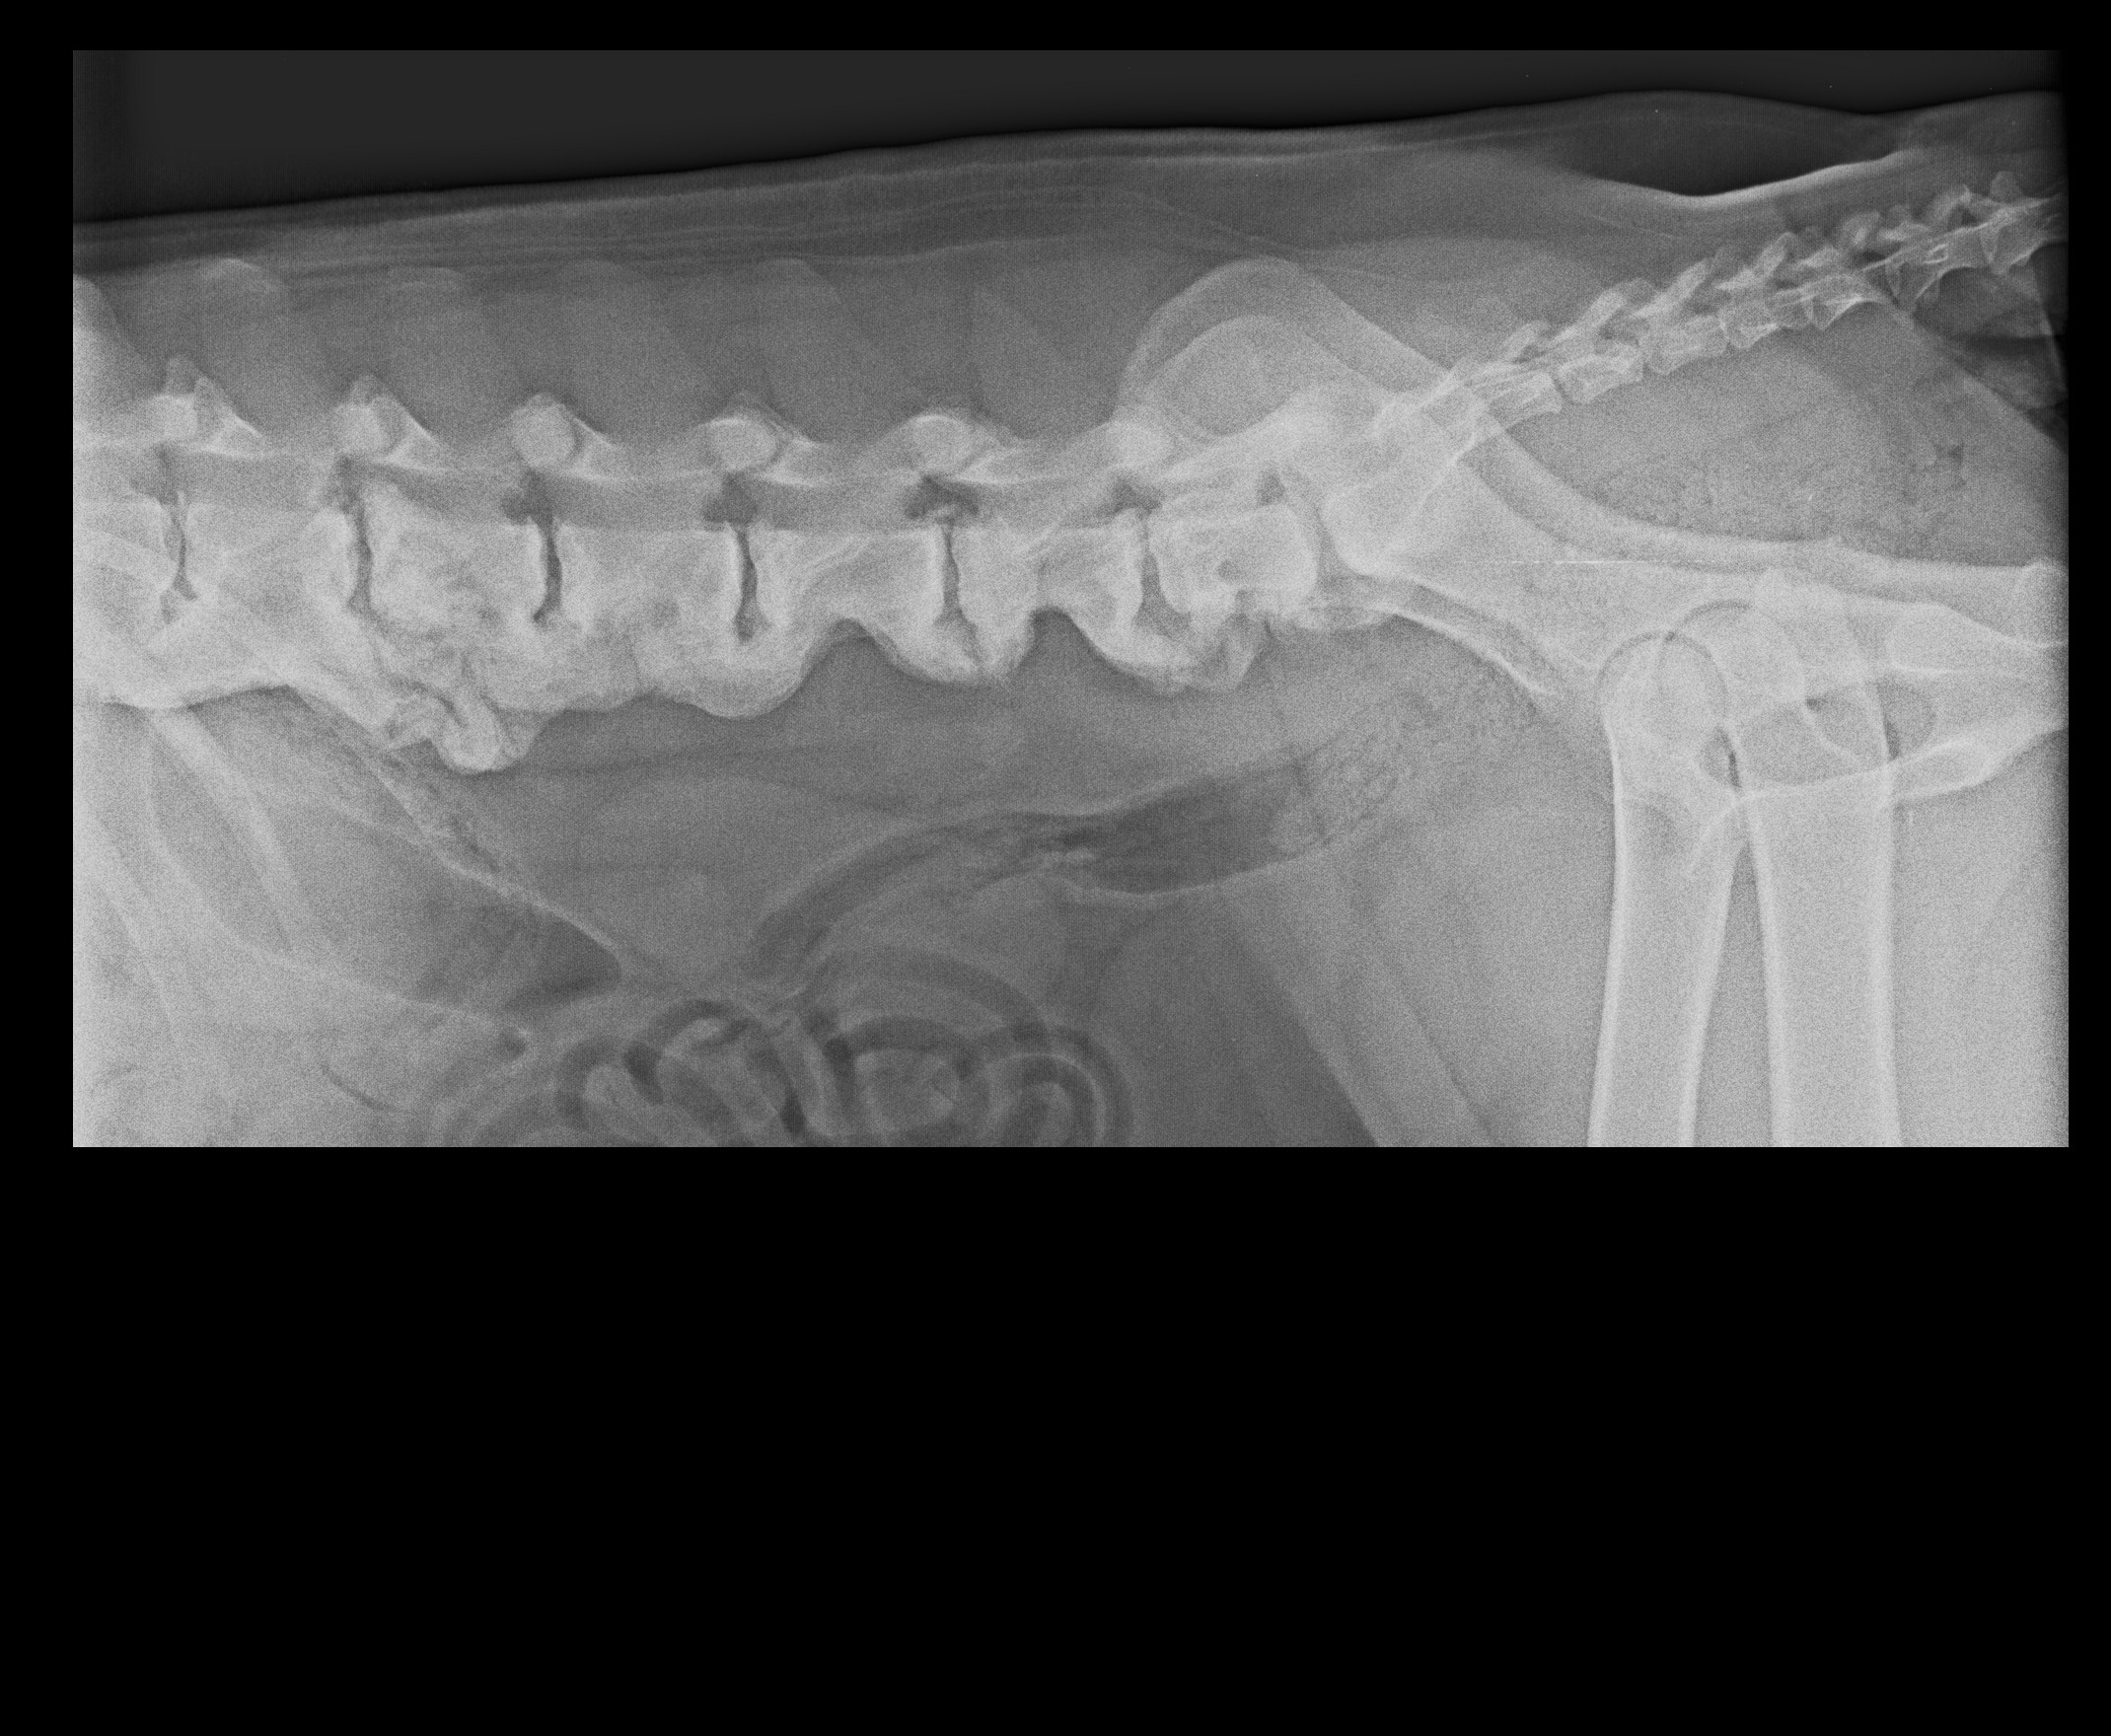

Akira, narodená cca február 2009, sa našla pri Lehniciach. V tejto lokalite je to už za posledný pol rok asi piata akita, takže je evidentné, že sa ich nejaký množiteľ zbavuje! Akira je dokonalou predstaviteľkou plemena americká akita. Má za sebou neľahké obdobie, prešla to totiž operáciou vyskočenej platničky, ktorej predchádzal život v krutých bolestiach :( Platnička je opäť na mieste, ale Akira má problém s celou chrbticou, ktorá je zrastená (prikladáme RTG snímky). Akira sa teda bude musieť doživotne šetriť, aby nemala zbytočné bolesti. To znamená kontrolovaný pohyb, určite nenechávať niekde na dvore bez dozoru, aby celý deň lietala! Prechádzky iba na vodítku, kľudne na dlhom, ale treba dať pozor aby nezabehla a nezačala sa hrať na naháňačku. Skákanie minimalizovať ako sa len bude dať, a ideálne žiadne schody! Akira si túto starostlivosť ale veľmi zaslúži :) Je to neopísateľný miláčik, lásky má na rozdávanie aj za troch. Miluje ľudí, úplne každého človeka zbožňuje, aj toho, ktorého ešte nepozná :) Na klinike si ju celý personál zamiloval a ona sa túlila ku každému. Akiru nám dokonale opísal pán doktor na klinike, ktorý povedal, že "je to miláčik, ale jadrový fyzik to nie je" :D Toto Akiru dokonale vystihuje ale to samozrejme neznamená, že sa nič nedokáže naučiť, len z nej nikdy nebude komisár Rex a ani Hatchiko :D Je to také milé trdielko, ktoré nechce nič iné, ako milovať a byť milovaná. Je nenáročná, nekonfliktná, znášanlivá so psíkmi aj fenkami, jednoducho dokonalá. Hľadá si rodinu, ktorá jej bude vedieť zabezpečiť potrebnú opateru a starostlivosť. Samozrejme konzultácia novej rodiny s ortopédom je možná. Akira čaká na svoju druhú šancu od februára 2017.

Akira, geboren ca. im Februar 2009, wurde in Lehnice gefunden. In dieser Umgebung ist das schon fünfte Akita in den letzten 6 Monaten, also offensichtlich werden die von ein Vehrmehrer rausgeschmissen. Akira ist typischer Darsteller von Amerikanische Akita. Sie hat schwere Zeiten hinter sich. Sie hat große Schmerzen im Rücken gehabt, ihre Bandscheibe wurde operiert. Bandwechsel ist wieder auf seinem Platz, aber Akira hat Problem mit dem ganzen Rückgrat (die RTG Bilder legen wir bei). Akira muss sich den Rest des Lebens schonen, damit sie keine unnötigen Schmerzen hat. Das heißt die Bewegung unter Kontrolle zu halten, kein freies Laufen am Hof ohne Aufsicht. Die Spaziergänge nur an der Leine, auch auf längeren, nur man muss aufpassen dass sie nicht laufen will. Springen muss so viel es geht minimalisiert, ideal keine Treppen. Akira verdient sich diese Sorgfalt :) Sie ist ein unbeschreibliches Liebling, Liebe kann sie für drei verschenken. Sie liebt sehr alle Menschen, sogar auch Fremde :) In der Klinik hat sie das ganze Personal geliebt. Akira wurde von Hr. Doktor so beschrieben: „sie ist ein Liebling, kein Kernphysiker“ Das heißt aber nicht, dass sie nichts lernen kann, aus ihr wird nur kein Kommissar Rex und kein Hatchiko werden. Sie ist so lieb und das einzige was sie will ist geliebt zu werden und jemanden zu lieben. Sie ist nicht anspruchsvoll, konfliktlos, erträgt sich mit anderen Hunden, einfach vollkommen! Sie sucht eine Familie die ihr die notwendige Versorgung geben kann. Selbstverständlich sind weitere Konsultationen mit einem Orthopäden möglich. Akira wartet auf ihre zweite Chance seit Februar 2017.